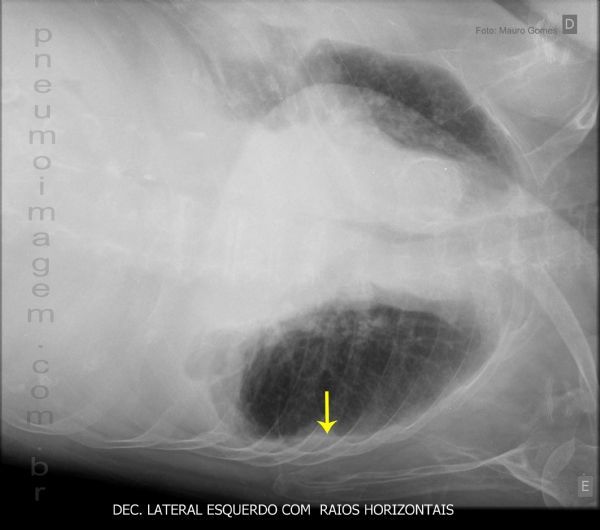

(Decúbito lateral com raios horizontais)

Se > 01 cm = derrame pleural importante.